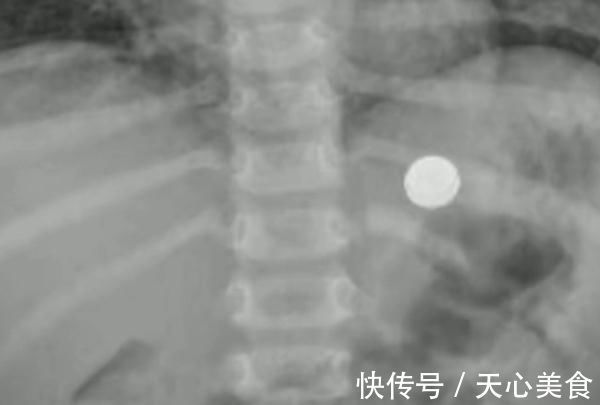

文章插图

一番检查后

医生马上进行了全麻手术

从孩子的胃里

拿出了一枚直径约1厘米的纽扣电池

而它也引发

孩子的胃部多发溃疡

“很庆幸的是,这颗电池在体内是一天,时间比较短;当时取的时候也比较顺利。”